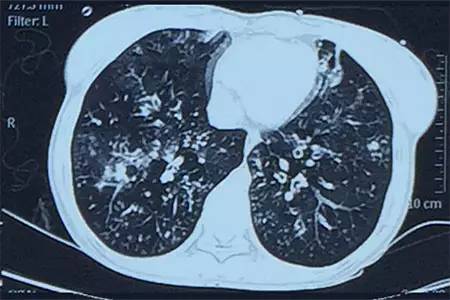

肺CT见下图

该患者肺部影像学表现为明显的支气管扩张,同时伴有弥漫的渗出斑片影,考虑合并感染,细菌学培养提示为绿脓杆菌,结合药敏结果给予头孢他啶+阿米卡星抗感染,患者存在II型呼吸衰竭予气管插管机械通气支持,加强体位引流排痰,治疗18天,患者情况好转出院。